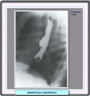

Divertículos del cuerpo esofágico Los divertículos del cuerpo esofágico se observan preferentemente en los dos tercios inferiores del esófago. Cuando se localizan en los 5 cm por encima del esfinter esofágico inferior, reciben el nombre de divertículos epifrénicos. En algunos casos estas lesiones son congénitas y representan una forma frustada de fístula esofageotraqueal. Los divertículos por tracción, poco frecuentes en los países desarrollado se deben a deformaciones o cicatrices del esófago resultantes de enfermedades inflamatorias crónicas del mediastino. Los divertículos del tercio medio del esófago suelen ser de pequeño tamaño, de forma redondeada y de cuello ancho, lo que explica que raras veces retengan alimentos. Son relativamente frecuentes. Las manifestaciones clínicas de los divertículos son muy variables y dependen fundamentalmente de su tamaño y localización. La mayoría de las veces son asintomáticos, pero del del cuerpo esofágico pueden ocasionar disfagia y a veces regurgitación, síntomas habituales del divertículo de Zenker. Los grandes divertículos del tercio medio del esófago también pueden producir disfagia y regurgitaciones El diagnóstico se establece por lo general radiológicamente. El contraste de bario permite ver con facilidad el tamaño y la situación de la bolsa diverticular. La endoscopia agrega escasa información, salvo en el caso de que se sospeche la presencia de un cáncer. Endoscópicamente, los diverticulos del tercio medio del esógafo suelen ser de pequeñas dimensiones y cuello ancho (*) Los divertículos epifrénicos suelen presentar un cuello estrecho aunque su tamaño puede alcanzar grandes proporciones (*) produciendo incluso una reducción de la luz esofágica. Como los divertículos epifrénicos son divertículos por pulsión, la pared diverticular está formada por una fina capa mucosa lo que aumenta el riesgo de perforación al practicar la endoscopia. TRATAMIENTO Los divertículos asintomáticos no requieren tratamiento. En los pacientes con disfagia o serios problemas de regurgitación está indicada la cirugía. En la mayor parte de los casos de divertículos epifrénicos, se practica una funduplicatura si la miotomía llega al esfínter esofágico inferior.